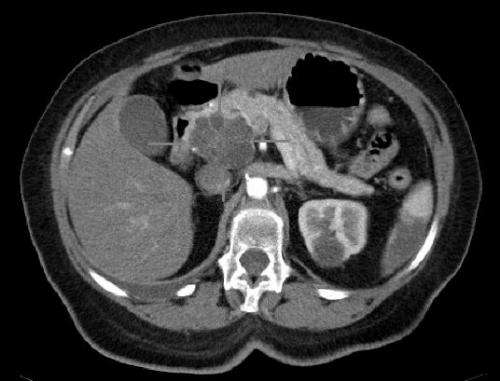

轴向CT图像与iv对比。胰头巨大腺腺癌。